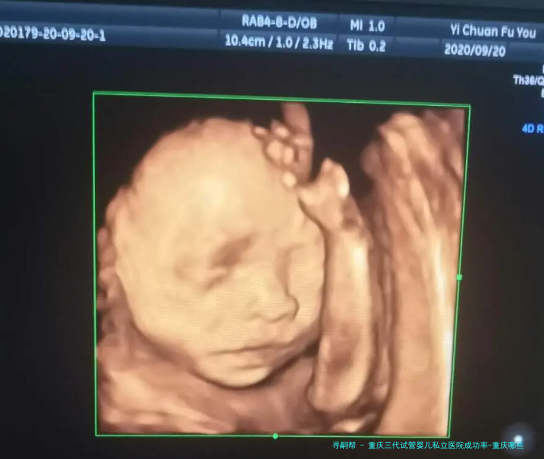

重庆三代试管婴儿私立医院成功率-重庆哪些医院可以做三代试管!

试管婴儿技术已然成为许多不孕夫妇实现生育心愿的有效途径。重庆作为国内西南地区的中心城市,拥有许多的医疗资金,其中私立医院在试管婴儿范围也取得了显着的成就。本文将关键要点推荐重庆三代试管婴儿私立医院的成功率以及相关信息。